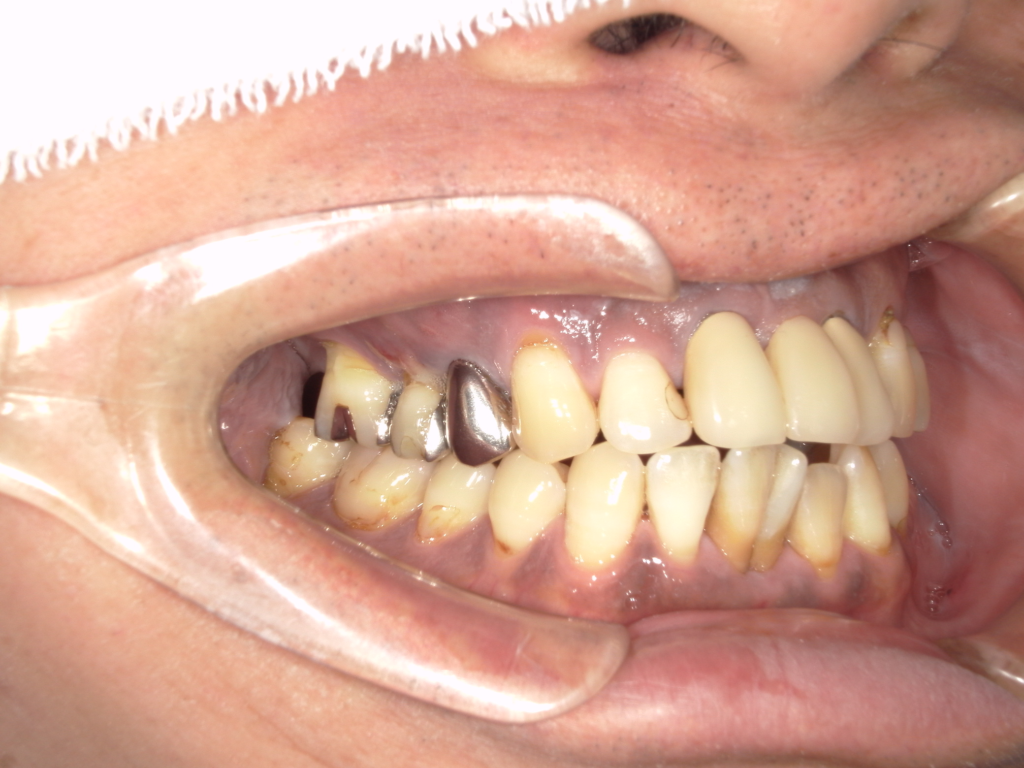

治療前

治療後